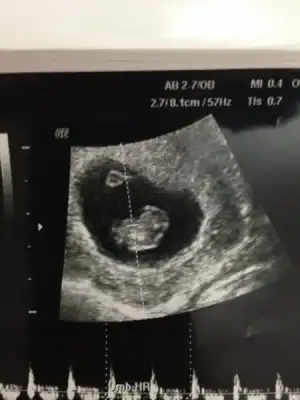

kız gibi canım. Şöyle usg resmini eline aldığında eğer karından usg ise bebek kesenin sağına yakınsa kız soluna yakınsa erkek, vajinal usg ise tam tersi. Buarada sesin ultrason resmi benimkine çok benziyo bebeğin kesedeki konumu olarak

Cnm ben tek sağ sol için yorum yapmıyorum plasentasına falanda bakıyorum hangi yöne yatkınsa hepsi, ona göre söylüyorum

Cnm bu konu başkasınındı o zaman tek sağ sol olarak yorum yapılıyordu ama ben plasenta, kese ve bebek hangi yönde ağırlıktaysa ona göre yorum yapıyorum. Önemli olan ilk USG resmi olsun 6,7,8 haftalık

Bu 8. Haftada karindan cekildi canim.yorumlarsan sevinirim

BİZİ de yorumlayabilir misiniz 8 haftalik usgmiz :KK66:) teşekkürler simdiden. Karindan usg.